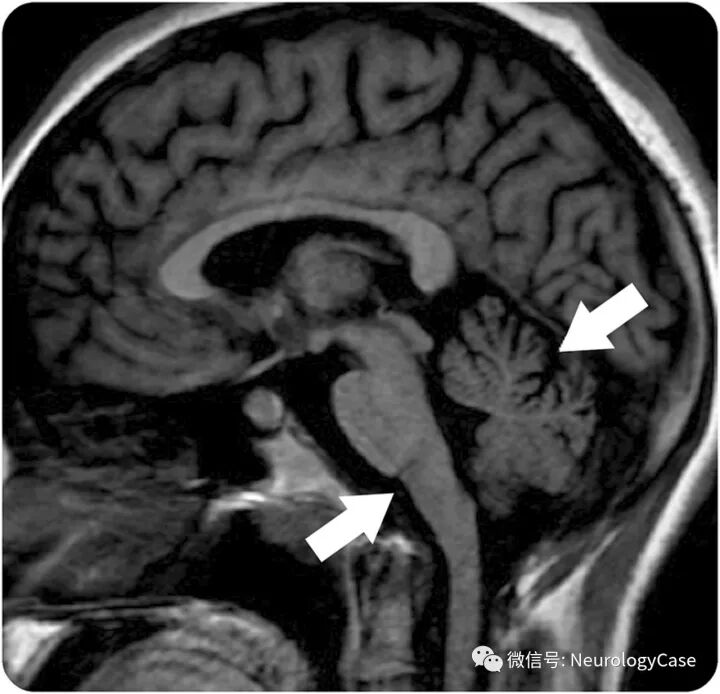

11岁女孩,表现为进行性认知功能下降和下肢肌张力障碍4年。父母非近亲结婚,且家族史无殊。查体提示构音障碍,全身型肌张力障碍(主要为下肢)和帕金森样症状,包括运动迟缓和姿势不稳。行走时躯干伸展,前臂屈曲,踮着脚尖摇摆前行,脚后跟并不接触地面,称为鸡步(视频1)。头颅MRI可见双侧基底节区,脑干及小脑核团T1WI高信号,提示锰蓄积(图1)。遗传学检测发现锰转运体SLC30A10基因纯合突变(c.922C>T;p.Q308X)。诊断为遗传性锰中毒。

(图1:A-C:T1WI可见双侧基底节,中脑和脑桥被盖部高信号病灶;D:矢状位T1WI可见中脑和小脑核团高信号;尽管基底节区T1WI高信号可见于铜蓄积,一氧化碳中毒,肝衰竭,高血糖以及褪黑激素蓄积,但也是锰中毒的典型改变)